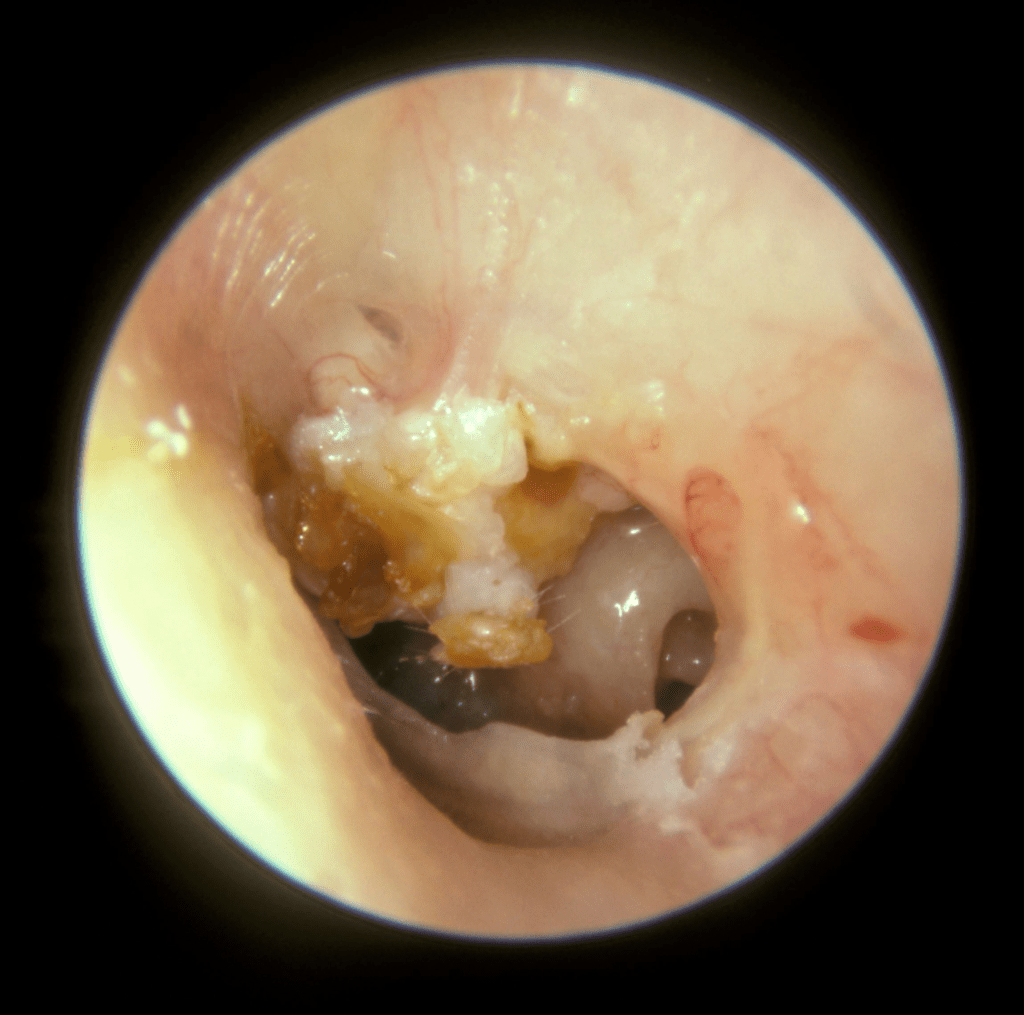

On distingue les OMC bénignes, ou non choléstéatomateuses, (otite séromuqueuse et otite moyenne chronique à tympan ouvert), qui peuvent laisser des séquelles tympaniques et ossiculaires accessibles au traitement chirurgical, et les OMC dangereuses ou choléstéatomateuses, qui n’ont aucune tendance à la guérison spontanée et peuvent entraîner des complications dont certaines mettent en jeu le pronostic vital.

- l’examen de l’oreille, pour vérifier l’état du tympan ;

- nettoyer complètement l’oreille moyenne ;